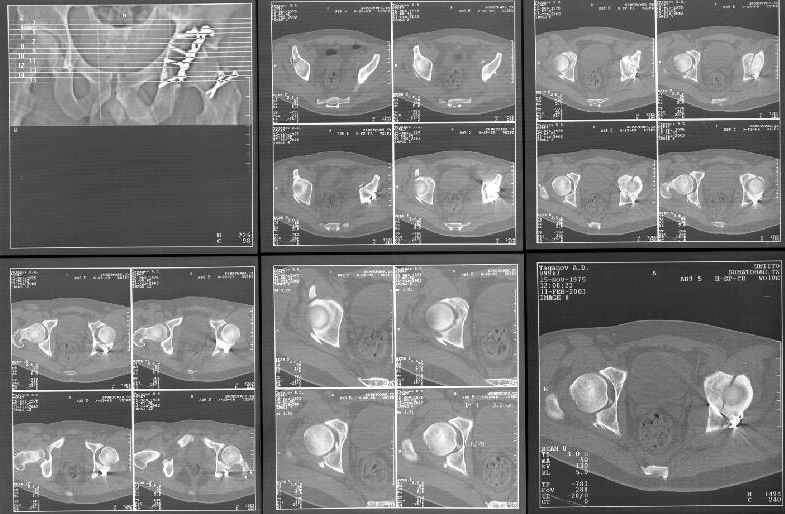

Пациент переведен в нашу клинику на 5 день после множественной травмы 25.01.2003 - двустороннее повреждение вертлужных впадин, разрыв левого крестцово-подвздошного сочленения. Вывихи обоих бедер. В месте первичного поступления подвздошный вывих правого бедра вправлен 26.01.2003, наложено вытяжение за левую вертельную область. Остеосинтез левой вертлужной впадины выполнен у нас 6.02.2003. Вопрос: надо ли синтезировать задне-верхний край правой вертлужной впадины?

правую впадину собрали здорово! Мои поздравления Рункову. Сами меня учили-учили, а где же запирательная проекция левой вертлужной

впадины. Такое впечатление что на КТ есть интерпозиция кусочком, тогда уж точно надо туда залесть, а так, я считаю не стоит.

Уважаемый Алексей, через месяц после повреждения обострять травму, чтобы продлить "колясочный" срок? Второй сустав станет опорным не скоро.Головка на Ртг концентрически вставлена, задний фрагмент не интерпонирует, лимбус,по видимому тоже, ямочный фрагмент мешать не должен,герметизирующую манжету адекватно восстановить, обычно, не удается. Выгоды от оперативного вмешательства сомнительны. Я бы оперировать не стал.Еще месяц без нагрузки (по меньшей мере) и в нашей "конторе"- МОНИКИ(Вы наверняка знаете О.Ш.Буачидзе) положились бы на ощущения пациента при активных движениях правым бедром. Можно и сейчас проверить на возможность блокады и тогда принимать окончательное решение.